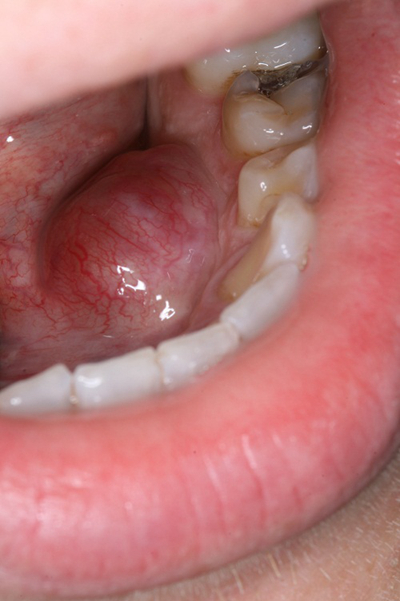

口腔癌圖片

口腔癌的前兆 (51)

口腔癌的前兆 (53)

口腔癌的前兆 (54)